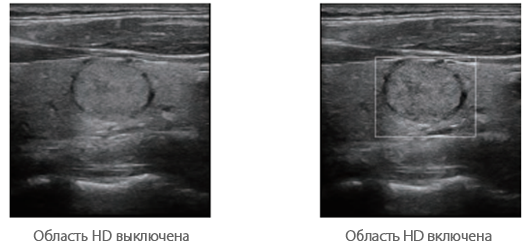

Улучшенная обработка канальных данных

Технология ZST+ обеспечивает улучшенную обработку канальных данных, что позволяет существенно повысить четкость визуализации. Многократная ретроспективная обработка канальных данных позволяет эффективно использовать акустическую информацию для улучшения качества изображений.

· Область HD: более четкое изображение в пределах области интереса.

· Когерентный пространственный синтез: дальнейшее улучшение качества изображения при пространственном объединении.